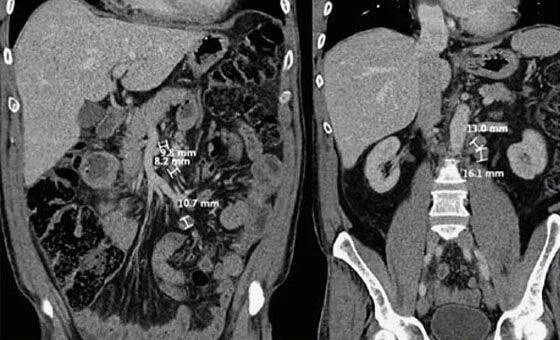

Воспаление брюшных лимфоузлов причины